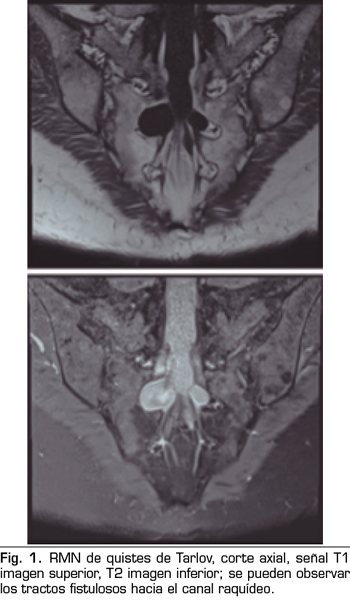

Se realiza una RMN donde no se observan alteraciones estructurales que justifiquen las dolencias que presenta. Como hallazgo casual se describen quistes de Tarlov a nivel de S2. Se solicita una valoración por el servicio de neurocirugía, quienes dudan que la clínica sea consecuencia de los quistes (Figuras 1 y 2).

Una de las causas de dolor crónico a tener en cuenta son los “quistes perineurales” o “quistes de Tarlov”. Desde su primera descripción en 1938, son numerosos los artículos en los que se hace referencia. Se trata de lesiones nerviosas que se producen más frecuentemente en la zona sacra (8). En un estudio de Paulsen RD sobre la prevalencia y el drenaje de los quistes de Tarlov, se observó que en 500 pacientes que se sometían a una Resonancia Magnética (RMN) por dolor lumbar, el 5 % presentaba quistes de Tarlov y un 20 % de esos pacientes padecían síntomas relacionados con ellos (9,10). El diagnóstico suele ser casual mediante RMN; la cifra es variable debido a que solo se solicita a aquellos pacientes que presentan dolor lumbar crónico. Dicha técnica es más sensible que la tomografía axial computerizada (11,12).

No obstante, debemos tener en cuenta las variaciones anatómicas como son los quistes de Tarlov, a expensas de las capas más internas de las meninges, la piamadre y el aracnoides. Estos quistes principalmente se sitúan en la zona sacra y lumbar, y suelen diagnosticarse de manera incidental en el transcurso de una RMN. Aunque la clínica producida por los mismos no es frecuente, se deben tener en cuenta como posible diagnóstico diferencial ante posible dolor lumbar crónico.